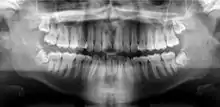

Panoramic radiograph

A panoramic radiograph is a panoramic scanning dental X-ray of the upper and lower jaw. It shows a two-dimensional view of a half-circle from ear to ear. Panoramic radiography is a form of focal plane tomography; thus, images of multiple planes are taken to make up the composite panoramic image, where the maxilla and mandible are in the focal trough and the structures that are superficial and deep to the trough are blurred.

A dental panoramic radiograph, showing the maxilla and mandible, all the teeth including the "wisdom teeth," the frontal and maxillary sinuses, the nasal cavity and the temporomandibular joint and other near by head and neck anatomy. | |